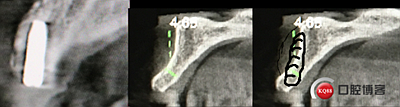

“以修復(fù)為導(dǎo)向”,在前牙種植體中心點(diǎn)就是未來牙冠舌側(cè)窩位置。那這個(gè)病例植體的方向和位置就只能是下圖右側(cè)這樣了。很明顯植體根尖部分要穿出唇側(cè)倒凹的。怎么辦?翻大瓣植骨蓋膜減張縫合?不!可以不翻瓣,大家仔細(xì)看看下圖右圖我畫的那條細(xì)細(xì)的弧線,是不是跟原來唇側(cè)凹陷的骨面成為左右對(duì)稱的兩條弧,也就是說骨膜從原來唇側(cè)凹陷骨面上剝離然后放到左側(cè)我畫的那條弧線那里根本不需要減張,這兩條弧線之間也就是唇側(cè)凹陷處放上骨粉,骨膜不會(huì)增加張力。不知道大家看明白了沒有。

術(shù)后4個(gè)月X光片。